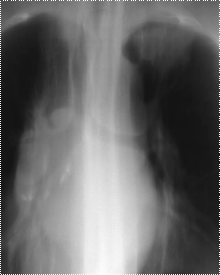

Характерной рентгенологической картины этого заболевания не существует, как не существует и предпочтительной локализации (Приложение А рисунок 8). При бронхиоло-альвеолярном раке встречаются, пожалуй, все известные в рентгенологии синдромы: это может быть солитарный периферический узел или пневмониеподобный инфильтрат, группа очагов, симулирующих туберкулез, прикорневое уплотнение, долевое или субдолевое уплотнение, уплотнение всего легкого, мелкоузелковая диссеминация и т.д. Среди этого многообразия наиболее часто встречаются три формы: узловая, пневмониеподобная и диссеминированная. Процесс может быть односторонним и двусторонним. Наиболее характерная картина наблюдается при пневмониеподобном солитарном образовании. При этой форме в рентгенологическом изображении определяется фокус понижения пневматизации неправильной формы, с нечеткими очертаниями, неоднородной структуры с наличием мелких участков просветления округлой или овальной формы, придающих картине опухоли ноздреватый вид. Подобные просветления не являются отображением деструктивного процесса, они обусловлены чередованием участков опухолевой инфильтрации с участками легочной ткани, сохранившей воздушность. Учитывая многообразие рентгенологических проявлений, решающее значение в диагностике бронхиоло-альвеолярного рака приобретает цитологическое исследование мокроты или пункционная и катетеризационная биопсия.